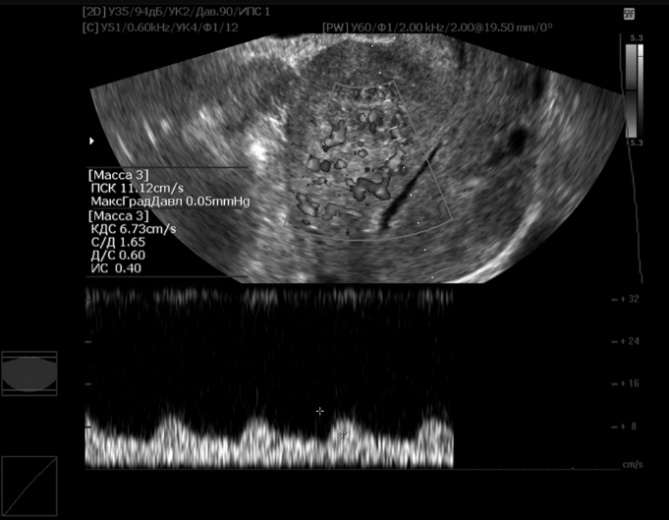

The thickness of the scar formed after metroplasty, as measured by ultrasound on the 6th-7th day after surgery in the group where PRP was applied, averaged 8.4±2.7 mm. Whereas, in the group without PRP, the average scar thickness on days 6-7 was 9.9±1.2, which was 1.6 times higher than in the comparison group. Apparently, the greater scar thickness was associated with delayed scar repair processes due to edema. Examination of the scar after 6 months showed a decrease in scar thickness in both subgroups, with the values falling within statistically non-significant differences compared to the control group (Fig. 2, 3). | Figure 2. Patient U., 27 years old, 6 days after metroplasty |

| Figure 3. Patient A., 25 years old, 6 months after metroplasty |